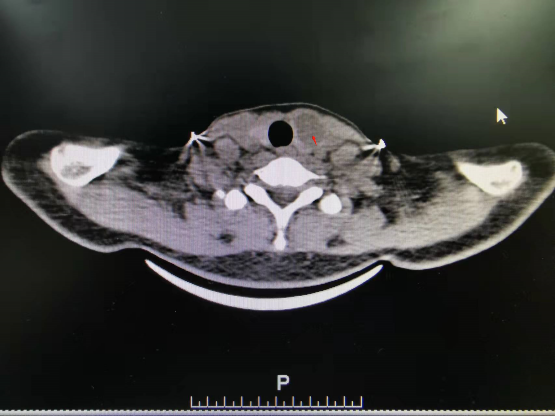

甲状腺结节是甲状腺内肿物的统称,多见于中青年女性。甲状腺结节分为良性和恶性两大类,大部分患者需要手术治疗。传统手术要在患者颈部切口,术后患者颈部会留下明显的手术疤痕,给患者造成很大的心理负担。随着腔镜技术的发展,术者对许多患者不再采用传统的开刀方式,而是采用非颈部入路,将颈部切口改为在胸前很低的乳晕位置开3个0.5厘米~1.0厘米的小孔,完成手术,有很好的美容效果,受到了患者的喜爱。 病例 董某,女,29岁,身高160厘米,体重50公斤。 主诉:发现颈前肿大1天。 现病史:患者1天前无明显诱因出现颈前肿大,无压痛、胀痛,无声音嘶哑,无呼吸困难等;彩超检查结果提示甲状腺结节,较大者约为24.4毫米×17毫米。为了寻求系统治疗,患者来到河南中医药大学第一附属医院就诊。患者神志清醒,精神尚可,颈前肿大,平时易怒,纳可,睡眠一般,二便尚可。 既往史:平素身体状况良好,无冠心病、高血压病、糖尿病、脑梗死、脑出血、肺结核病史。患者说自己没有肝炎,没有手术史、输血史。 一般情况:体温36.6摄氏度,脉搏70次/分,呼吸19次/分,血压113/75毫米汞柱(1毫米汞柱=133.322帕)。 查体:颈软,无抵抗感,双侧颈动脉无异常搏动,颈静脉未见异常,气管居中,肝颈静脉回流征为阴性;甲状腺左叶Ⅰ度肿大,边界尚清,质中等,活动度欠佳,甲状腺右叶未触及异常,双侧未触及明显肿大淋巴结。 甲状腺功能:促甲状腺激素为3.73国际单位/升,甲状腺过氧化物酶抗体为0.6国际单位/升,血清游离三碘甲腺原氨酸为5.72皮摩尔/升,血清游离甲状腺素为12.21皮摩尔/升。 胸部CT检查结果提示左肺上叶有少许陈旧性索条。头颅CT检查结果提示无异常。 甲状腺CT检查结果提示甲状腺左叶体积增大,有结节样低密度影,有点状钙化灶。 术前诊断:甲状腺结节。 2022年2月22日,河南中医药大学第一附属医院普外腔镜微创外科主任张楠带领团队,为患者实施了腔镜下左侧甲状腺癌根治术+中央区淋巴结清扫术。术后第一天,患者无声音嘶哑、无饮水呛咳、无肢体麻木等不适,能自主下床活动,恢复良好。 术后病理检查结果提示(左侧甲状腺)甲状腺乳头状癌并发结节性甲状腺肿伴囊性变。 与传统手术相比,腔镜甲状腺手术具有以下优点:在患者的颈部看不到疤痕,具有美容效果;在腔镜下手术视野更清晰,定位更准确,并且患者出血很少,术后恢复快,能很快下床活动,住院时间短。 哪些患者可以进行腔镜甲状腺手术?结节性甲状腺肿或甲状腺腺瘤,最大直径<5厘米的患者;Ⅰ度肿大以内的原发性或继发性甲亢患者;低危分化型甲状腺癌,未侵犯邻近器官,无淋巴结肿大,有强烈的美容愿望的患者;甲状旁腺功能亢进症患者。 甲状腺癌通常恶性程度不高,大多数是“惰性肿瘤”,是一种“温和”的癌症,很少发生转移,进展也不快,且预后良好。甲状腺乳头状癌患者的10年生存率达到95%以上,通过规范手术及治疗可实现临床治愈,预后生存期通常可达到数十年。 (作者供职于河南中医药大学第一附属医院)